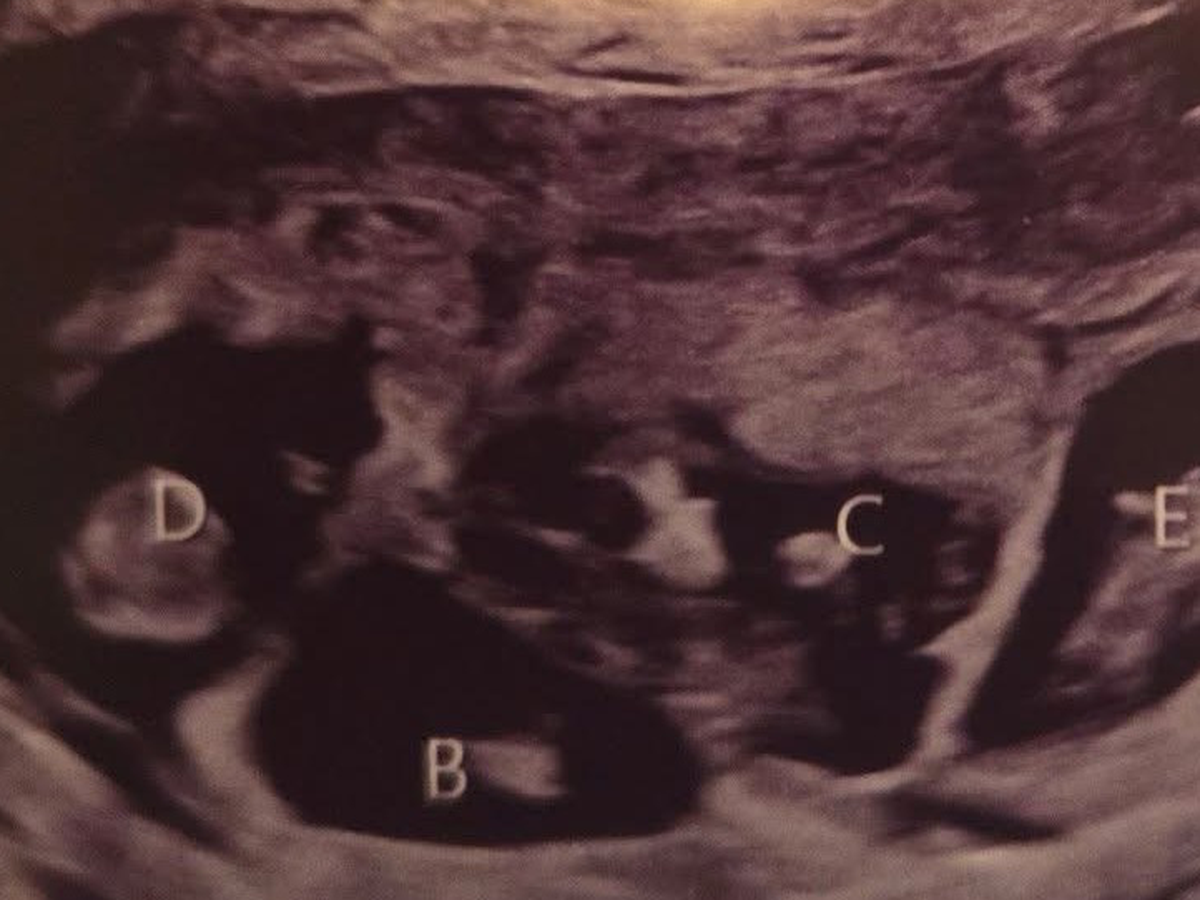

Jess is an amazing mother to her two young daughters, Hannah and Brooke, and a dedicated wife to the love of her life, John. They recently decided to expand their family and went through some fertility treatments. It was not IVF. She spontaneously released five eggs and all five were fertilized. Once again, this was not an intentional thing, nor is it something that could’ve been predicted. So now she is almost 20 weeks pregnant with quintuplets! For those of you who don’t know, that is five babies tucked safely away in her belly. The babies are thriving; they’re growing at appropriate rates, and as of right now, there’s no sign of major complications.